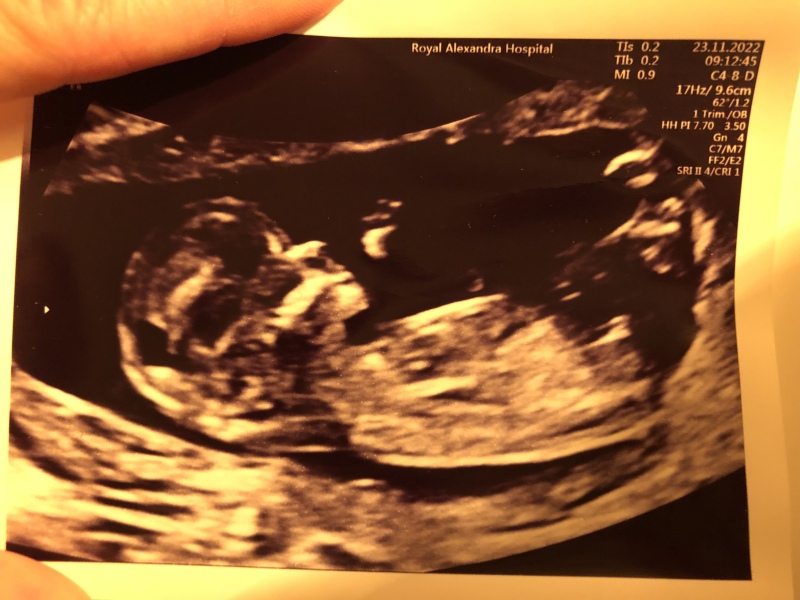

@jadel16 here is my scan xx

Nub theory wrong!

@Zaralina1 I'm not sure. I'm 50/50 on this will you let us know x